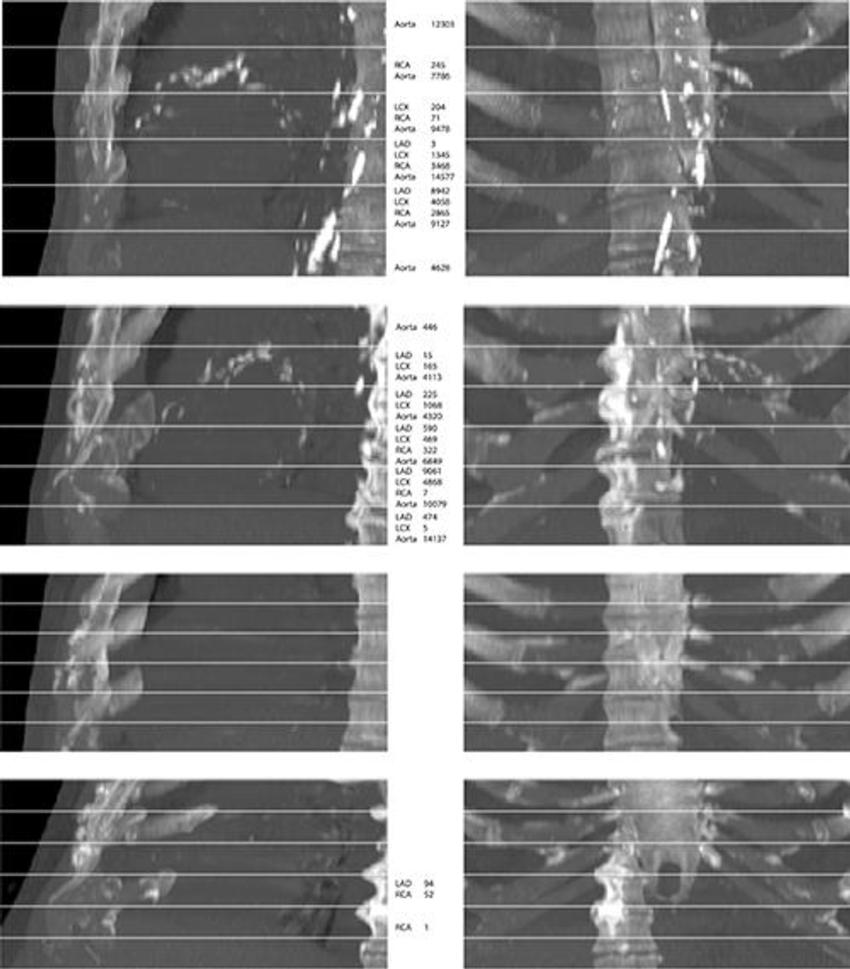

Figure 4. From top to bottom, maximum intensity projections of four randomly selected images from the evaluation set. The top two rows show cases that contain extensive arterial calcification (mainly the aortic arch), and the bottom two rows show controls containing none or limited arterial calcification. The left and right columns show maximum intensity projections of respective sagittal views and coronal views. The middle column lists Agatston scores if present in the slab. Note that none of the examples contained valve calcifications. Images have been automatically aligned such that they mimic the field of view of cardiac CT. However, for visualization purposes, large parts of the ribs and the vertebrae have been manually cropped from these examples. LAD = left anterior descending artery, LCX = left circumflex artery, RCA = right coronary artery.